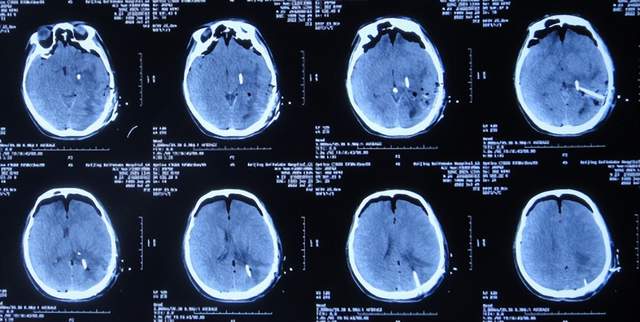

入院治疗21天即2022年8月8日(脉络丛切除术后18天),查头颅CT未见异常(图-37),患者身体无异常(图-38)。

图-37:2022年8月8日头颅CT

图-38:2022年8月8日

2022年8月22日(脉络丛切除术后32天),查头颅CT示颞角未见扩张(图-39),给予夹闭引流管。

图-39:2022年8月22日头颅CT

夹闭引流管14天后即2022年9月5日(脉络丛切除术后46天),查头颅CT示未见异常(图-40)。

图-40:2022年9月5日头颅CT

夹闭引流管15天后即2022年9月6日(脉络丛切除术后47天),给予拔除了脑室外引流管,当天查头颅CT示脑室基本正常(图-41);患者身体无异常。

图-41:2022年9月6日头颅CT

拔除了脑室外引流管后6天即2022年9月12日, 查头颅CT示未见异常(图-42);身体一切正常,于2022年9月16日出院。

图-42:2022年9月12日头颅CT

五、出院后随访

出院后3个月即2022年11月,在当地医院查头颅CT示无异常(图-43);本人叙述身体一切正常。

图-43:2022年11月头颅CT